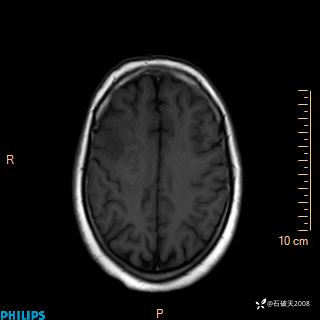

2020.11.14MR

FLAIR